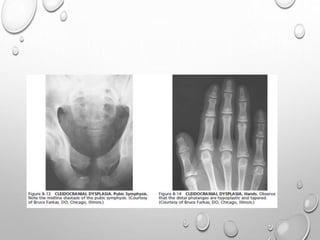

CLEIDOCRANIAL DYSPLASIA

AD

MUTATION OF CHR 6

FAULTY OSSIFICATION OF INTRAMEMBRANOUS AND

ENCHONDRAL BONES

PELVIS

SMALL , UNDERDEVELOPED PELVIC BONES

SYMPHYSIS PUBIS FAILS TO APPROXIMATE ANTERIORLY

FEMORAL HEAD : CHEFS HAT

COXA VALGA DEVELOPS INTO COXA VERUS

EXTREMITY

LONG BONES OF EXTREMITIES ARE LESS COMMONLY INVOLVED

MOST MARKED CHANGES ARE NOTED IN HAND

ACCESSORY EPIPHYSES FOR BASE OF 2ND METACARPAL …ELONGATE

DIGITS.

DISTAL PHALANGES ARE TAPERED , HYPOPLASTIC

SHORT HEIGHT BUT DWARFISM IS NOT COMMON